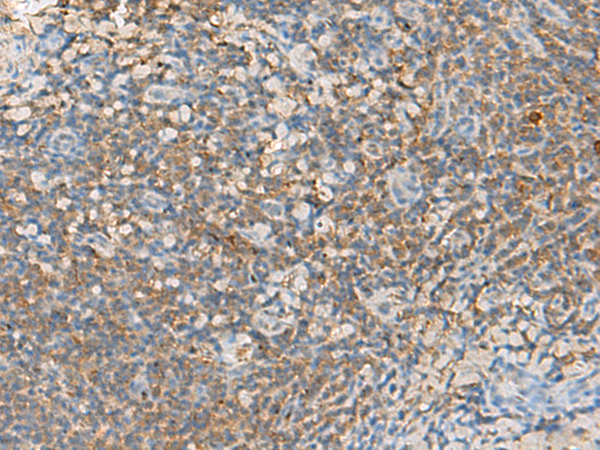

分类: 科研抗体货号: P13526别名: GIR; GPR72应用: IHC反应种属: Human, Mouse